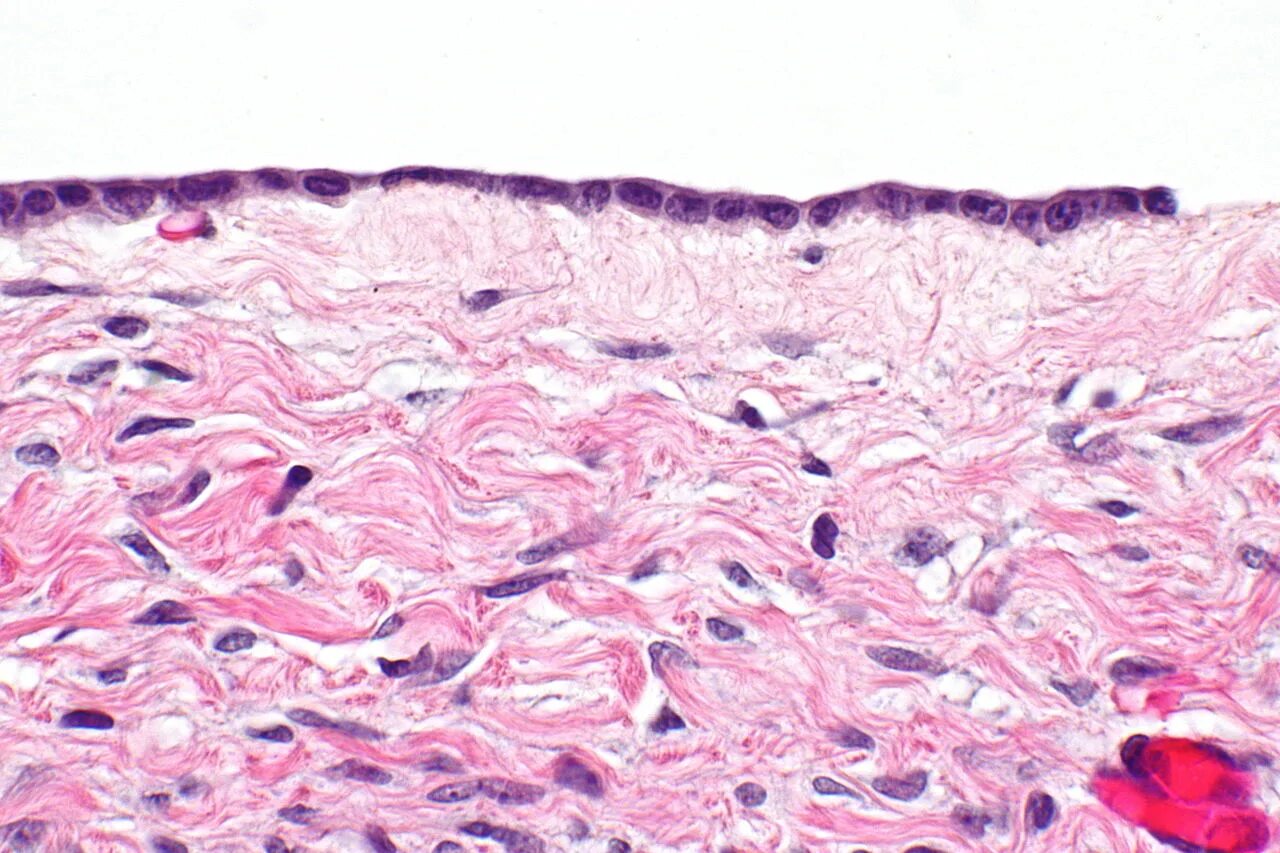

Гистология цистаденомы